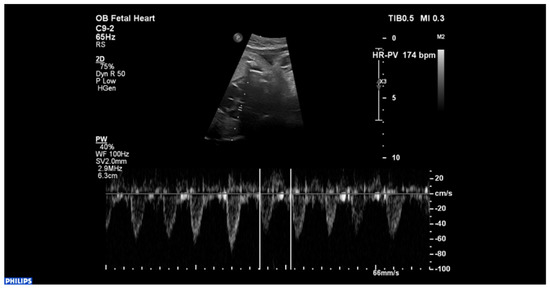

2. Case Description